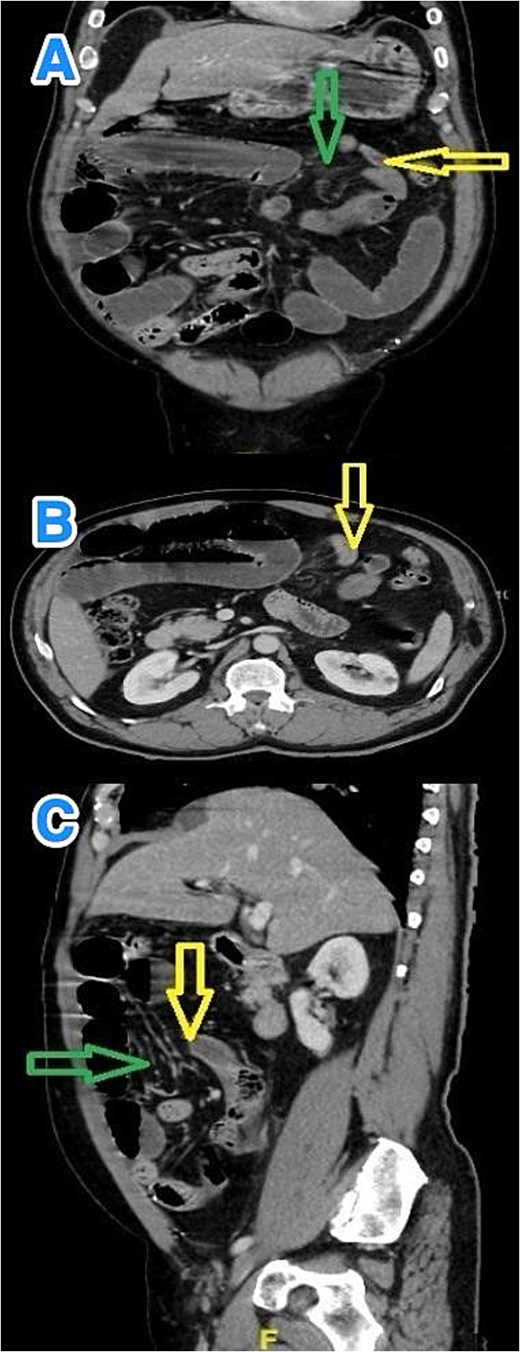

Contrast-enhanced abdominal computed tomography (CT) revealed multiple dilated small bowel loops, measuring up to 3.8 cm in diameter, along with air-fluid levels. The terminal ileum appeared elongated, and distal ileal loops were clustered in the left upper quadrant. A transition point was identified just proximal to these loops, raising suspicion for an IH rather than an adhesive obstruction, and signs of bowel fatigue were present. No free intraperitoneal air, lymphadenopathy, fluid collections, or peritoneal implants were noted (Fig. 1).

Multiview contrast-enhanced CT images of the abdomen demonstrate: (A) a coronal view showing herniated bowel (yellow arrow) through the greater omentum (green arrow), (B) an axial view showing the transition zone (yellow arrow), and (C) a sagittal view showing herniated bowel (yellow arrow) through the greater omentum (green arrow).